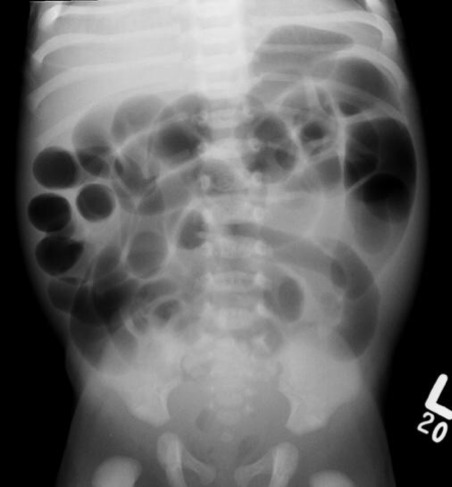

Abdominal x-ray